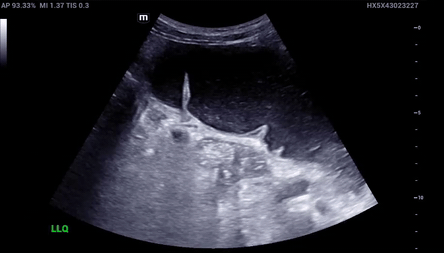

LBO: Ultrasound Findings

Diameter/Thickness

LBO on ultrasound will show a diameter of > 4.5 cm and thickness > 3 mm. The bowel wall is typically ≤ 3mm and ≤ 2 mm when distended

Haustra

Haustra are spaced and far apart. This differs from the plicae circulares of the small bowel.

A Lines

A-lines are reverberation artifacts seen on Ultrasound when beams interact with air. If seen inside the bowel, indicative of air-fluid levels inside bowels.

Abnormal peristalsis

“To and fro” movement of peristalsis indicative of obstruction. Normal peristalsis will have unidirectional flow

!!!Ultrasound has also been specifically evaluated for the diagnosis of LBO with a sensitivity of approximately 85% in one study!!